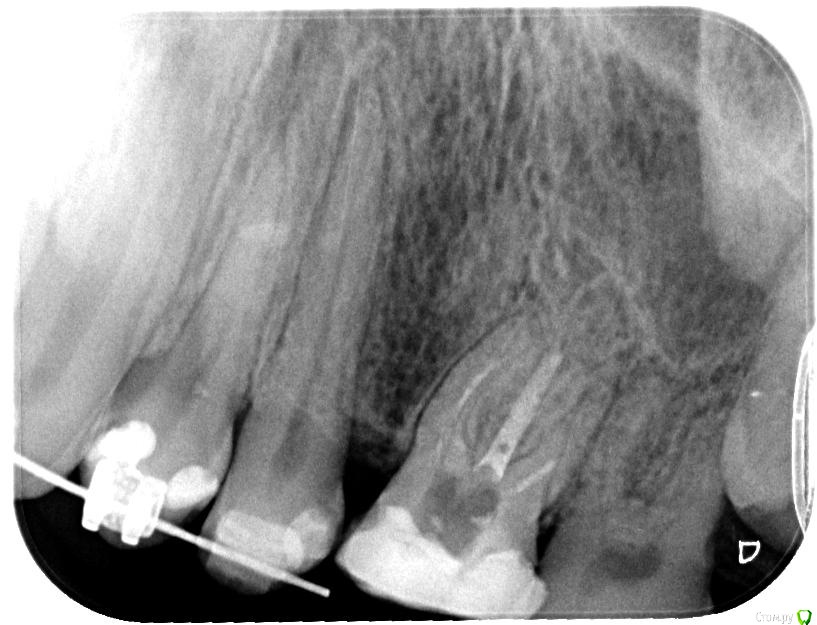

Axel_R Опубликовано 6 сентября, 2018 Автор Поделиться Опубликовано 6 сентября, 2018 Вот снимки на сегодня, зуб 26. Что скажете? Настаивать на высверливании старого материала из каналов или можно его спокойно оставить без негативных последствий? На зубе потом будет коронка. 1 1 Ссылка на комментарий

Axel_R Опубликовано 12 сентября, 2018 Автор Поделиться Опубликовано 12 сентября, 2018 Апдейт: Прошли 3 канала из 4, включая широкий небный. В оставшемся тонком канале говорят старый материал очень плотный и не поддается. На КТ и на снимках воспаления в районе верхушек тонких накалов не наблюдают и в других местах его тоже не видят. Форсировать не хотят, опасаются таки сделать перфорацию в тонком изогнутом канале. Поэтому доктор принял решение его оставить как есть и пломбировать пройденные. Ну Ок, им виднее. Но дело в том что зуб все еще болит когда кусаю что-то твердое! И никто не может назвать причину боли. Всегда думал сначала определяют в чем причина и устраняют эту причину, а уже потом пломбируют (ну как с кариесом). Я конечно мало в этом понимаю, но мне кажется если сейчас «замуровать» все вместе с источником боли, то ведь потом до этого источника уже будет не добраться (если он внутри канала или корня). А вдруг болеть будет еще неограниченно долго? Ведь не для этого я это лечение начинал…Я понимаю, что на повторное эндо нет гарантии и согласился с этим в документе, но как-то боязно... Вопрос: Правильное ли это решение? Соглашаться ли мне на пломбировку всех каналов когда зуб все еще болит? Ну или не соглашаться на завершение повторного эндо пока не устранят когда кусаю твердое? Какие будет мнения?Сама по себе пломбировка может устранить боль? Пока хожу с временной пломбой.На фото зуб в конце лечения с инструментами. Ссылка на комментарий